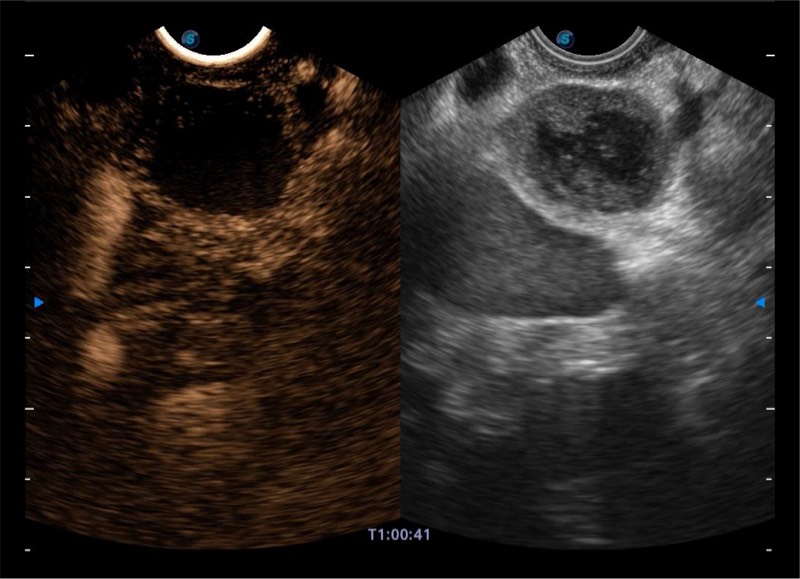

基于二十年的超声技术积累,玖鼎集团提供了最新一代的独立超声主机,在提供高质量图像的同时满足多学科使用。具备常见多普勒技术并提供弹性成像、声学造影等高端影像技术。新一代传感器具有更强的抗干扰能力并减少图像伪影。

4-12MHZ宽频输出